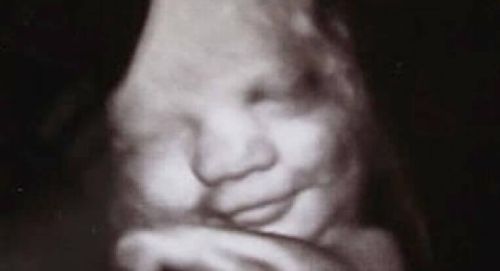

Niewiele jest rzeczy na świecie tak tajemniczych jak emocje. To prawda, że są cząstką naszej kultury, edukacji, płci i kraju pochodzenia. Jednak są one zintegrowane już z naszą bazą genetyczną. Uniwersytety w Durham i Lancaster (oba w Anglii) przeprowadziły fascynujące badania, które miały na celu wykazanie tego, czym są emocje. Podczas tego badania zaobserwowano, że już płód rozwijający się w macicy matki wyraża niewielką różnorodność emocji.

Dzięki zastosowaniu ultradźwięków udało im się odkryć, że nienarodzone dzieci się uśmiechają, a nawet, że przybierają grymasy twarzy związane z płaczem. Dowodzi to, że nawet w spokojnym i cichym wszechświecie, jakim jest macica, emocje już zaczynają „aktywizować” ludzi. Rozpoczyna to trening w tym instynktownym i niezbędnym języku, który zagwarantuje im przetrwanie.

Pojedynczy uśmiech pomoże być dowodem na dobre samopoczucie i zadowolenie. Płacz może spełnić swoją funkcję skutecznego „systemu alarmowego”. Dzięki niemu dziecko może wyrażać najbardziej podstawowe potrzeby.